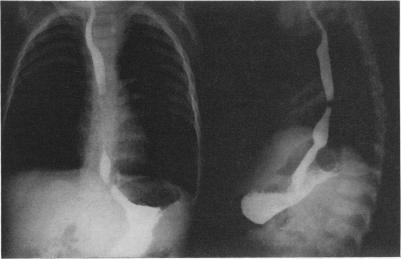

https://cdn.ncbi.nlm.nih.gov/pmc/blobs/5a03/1397071/d39e137615ad/annsurg00402-0089-a.jpg